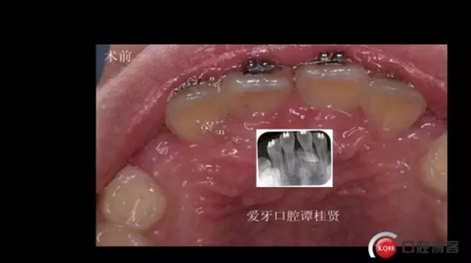

三年半前,家長領(lǐng)著小孩前來要求矯正牙齒,男,約八歲,兩中切牙間隙約12MM,有一多生牙,全景片顯示深處還橫著一顆,也許正處叛逆期,小孩非常的調(diào)皮,經(jīng)過幾次的各種哄和商談,也可能為了好看,終于勉強同意先拔掉露出的多生牙,前牙片斷弓關(guān)閉間隙

拔掉一顆后大概大半年時間很快就把間隙關(guān)閉了,但是由于還有一顆橫在兩中切牙間,牙縫始終得不到完全關(guān)閉,此時只能拔掉深部埋伏阻生的牙才能進一步矯正治療,但小孩一聽又要做一次手術(shù)有不同意了,這樣又拖了兩年多,長大了一些自然懂事了些。